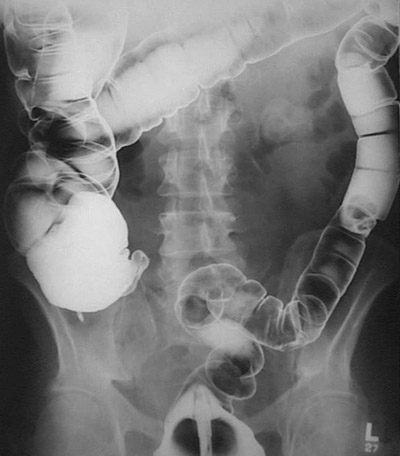

This barium enema reveals a polyp located midway down the descending colon. The polyp appears to be attached via a short stalk to the mucosa.